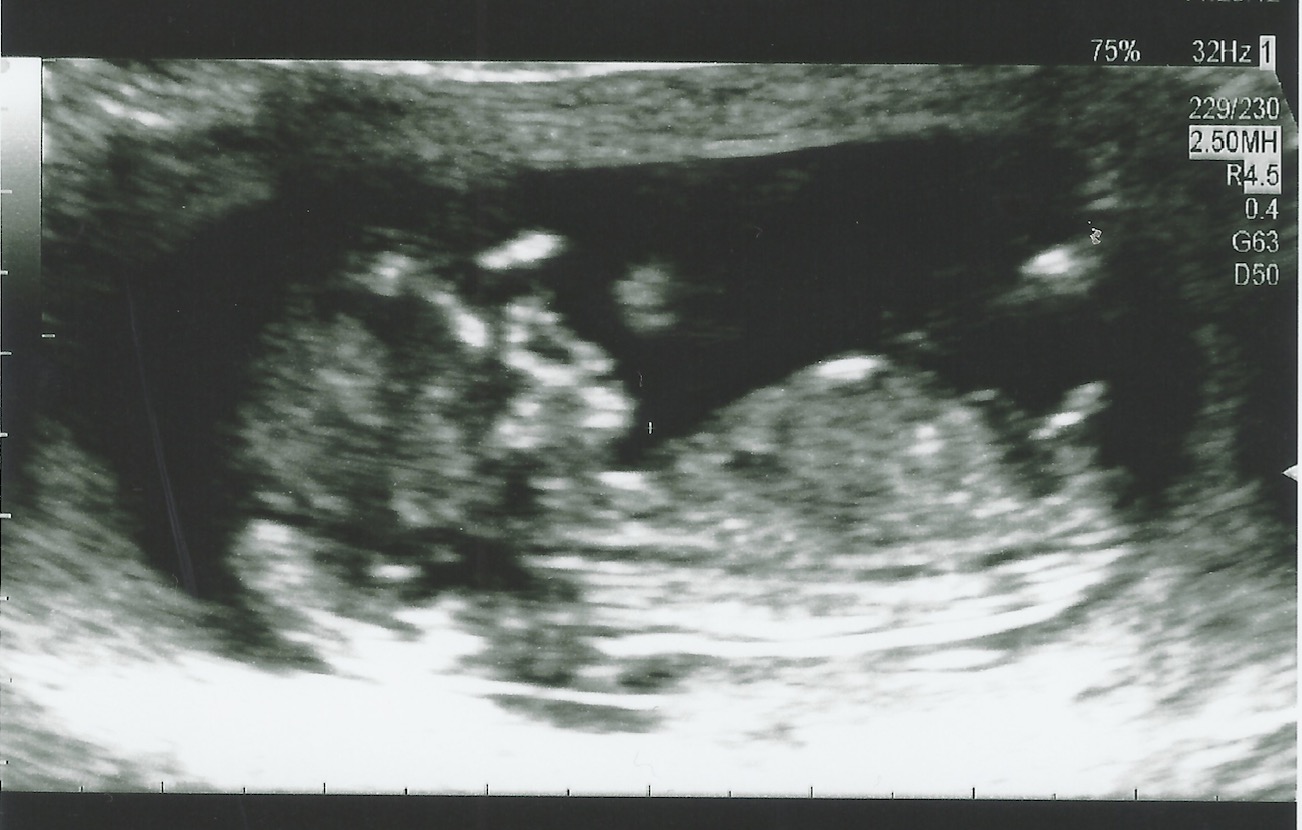

Hi ladies, I just had my 12 weeks 3 days first ultrasound scan today. It was very exciting to see the heart beating and the baby move, got the picture, but I can hardly guess anything - the sonographer said it is a very good picture! Any predictions? :happy: